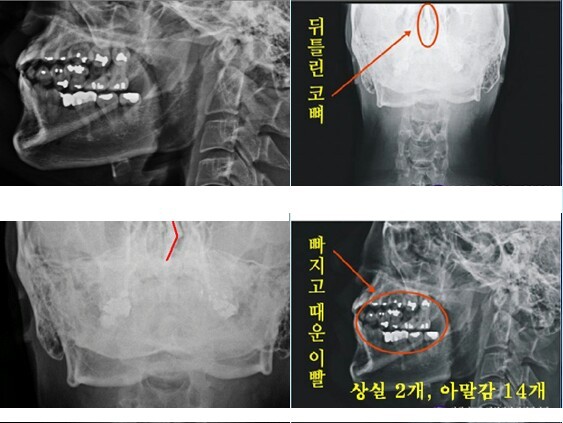

다른 하나는 자생병원에서 찍은 박주신씨의 엑스레이 치아사진을 보면, 아말감 치료를 받은 치아가 무려 14개나 된다는 점이다. 치과의사 문준식씨는 2005년 7월부터 2013년 8월까지 박주신씨를 치료했다고 주장했는데, 1990년대 이후 서울시에 있는 치과 중 아말감으로 이렇게 많은 치아를 치료한 경우는 거의 없다.

- ▲ ▲박주신씨 명의의 치아 엑스레이(X-Ray). 구외 X-Ray 상에 나타나는 각종 의혹은, 허리 MRI와 더불어 해당 피사체가 주신씨가 아닐 가능성에 무게를 더한다.ⓒ 사회지도층병역비리감시단

박주신 치과진료기록이 던지는 의문들박주신씨의 치과진료기록도 풀리지 않는 미스터리로 남아있다. 양승오 박사 등에 대한 검찰의 수사가 진행되던 지난해, 이 사건 피고인들은 박주신씨의 치아가 보이는 구외 X-Ray(이하 치아 X-Ray)를 근거로, 박주신씨의 신체를 촬영했다는 X-Ray 속 피사체가 제3의 인물일 가능성을 주장했다.

피고인들이 치아 X-Ray를 근거로, '피사체 바꿔치기' 의혹을 강하게 제기한 이유는, X-Ray에 나타난 치아의 상태가, 도저히 20대 중반 청년의 것이라고는 보기 힘든 특징을 갖고 있었기 때문이다.

주신씨 구외 X-Ray 사진을 보면, 치아 상태가 매우 불량하다는 사실을 알 수 있다. 치아 2개는 아예 없고, 아말감으로 때운 치아가 무려 14개에 달한다.

주신씨의 치아 아말감 치료와 관련돼, 김우현씨는 “혹자는 아말감 치료를 10개 이상 한 게 무슨 대수냐? 하면서 무시하는 경향이 있지만, 이는 모든 인과관계와 사실들을 무시하려는 것”이라고 비판했다.주신씨의 구외 X-Ray는 그가 허리 MRI를 촬영하면서 같이 찍은 X-Ray 사진들 중에서 치아가 보이는 X-Ray 사진이다.

따라서 구외 X-Ray 상에 나타나는 각종 의혹은, 허리 MRI와 더불어 해당 피사체가 주신씨가 아닐 가능성에 무게를 더한다.

주신씨의 구외 X-Ray 사진 상에 나타나는 의문들은, 양승오 박사 등이 주신씨의 병역비리 의혹을 제기하게 된 핵심 요인 중 하나였다.

치아의 치료상태는 매우 불량하고, 심지어 골반 X-Ray 사진에서는 골절된 뼈조각까지 발견됐다.주신씨의 것으로 알려진 치아 X-Ray 사진을 본 치의학 박사 C씨의 소견이다

“자료를 보면 2개의 이빨은 아예 없고, 아말감으로 때운 치아 14개가 보인다.

게다가 환자는 하악 1소구치(아래 어금니 앞쪽)까지 아말감으로 치료했다.

(젊은 사람이) 이런 경우는 매우 드물다.”“특히 전체적인 치료 상태를 보면, 소위 말하는 [야매]로 했을 가능성이 높다.

최근 국내에서 교육받은 치과의사의 치료라고 생각할 수 없을 정도다.

45번, 46번 보철 치료 및 치아 상실 문제에 있어서도 마찬가지다.

보철물로는 상당히 저렴한 비귀금속 합금을 사용한 것으로 보인다.

37번 치아는 아예 없는 상태로 방치하기도 했다.”“박주신의 가정환경을 고려하면, 이런 치료를 받았을 가능성은 1%도 안 된다.

서울 방배동에 거주했던 중산층 이상의 가정에서는 흔치 않은 상황이다.”